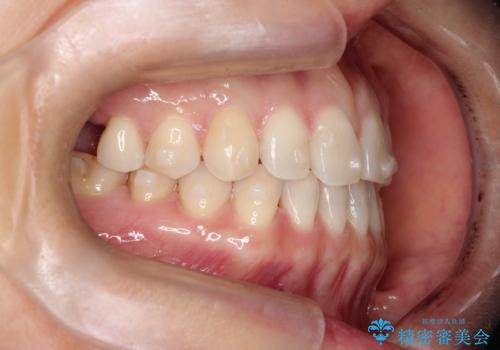

【インビザラインで再矯正】マウスピース矯正で隙間を閉じたい

- 過去に矯正を行ったあと、前歯の後戻りを主訴に来院されました。

マウスピース矯正にて隙間を閉じる計画をたて、治療を行いました。